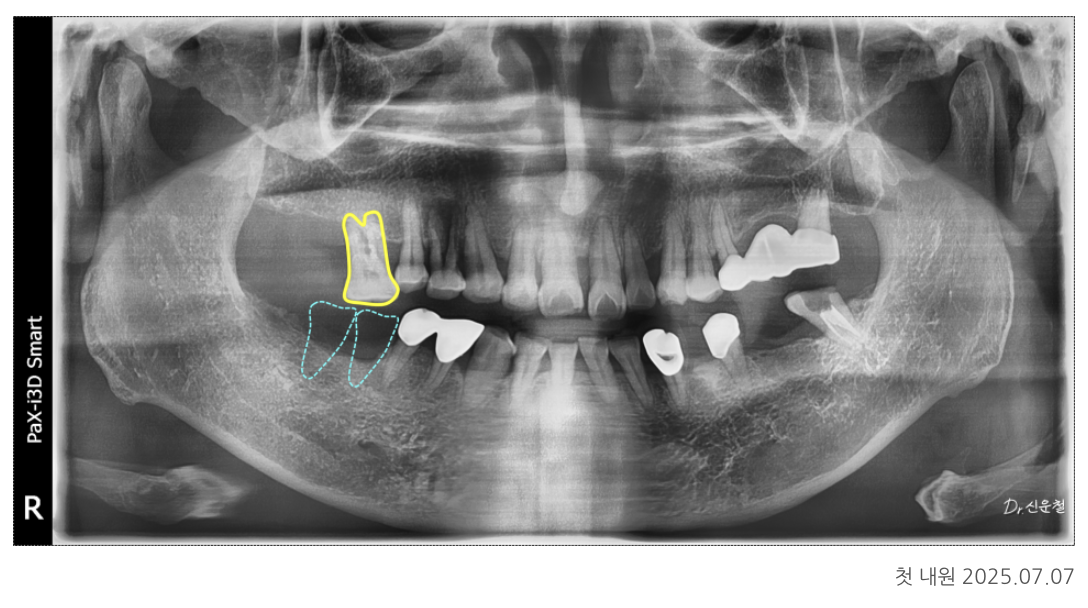

첫 촬영(파노라마·구강 사진)에서 크게 4가지 문제가 확인됐습니다.

① 아래 어금니 상실 → 위 치아 정출(내려옴)

오래전 빠진 아래 어금니 때문에

맞물리는 위 치아가 천천히 아래로 내려오는 정출이 진행되어 있었습니다.

치아는 상대 치아가 없어지면

균형을 잡는 힘이 사라져 자연스럽게 내려옵니다.

특히 어금니에서 정출되면 주변 치아까지 기울어지는 속도가 빠릅니다.

② 앞니가 제자리에서 벗어난 ‘전위 치아’

위 앞니는

잇몸 약화

치아 사이 공간 증가

한쪽 방향으로 반복된 씹는 습관

때문에 앞쪽으로 밀려 나온 상태(전위)였습니다.